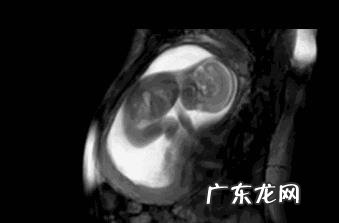

文章插图